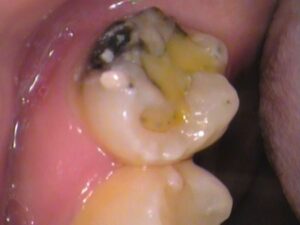

場所は、上の奥歯の頬っぺた側に虫歯がありました!

お口の中を見てみると、

すごく黒くなっていますね・・・(*_*)

上の奥歯はご自身では見えませんし、

さらに頬っぺた側は、頬っぺたが邪魔をして自分では見えづらい場所となります。

また歯ブラシも意識して磨かなければ磨けないところです。

汚れが残り、虫歯が徐々に進行していきます。

通常通り治療を進めます。

局所麻酔をして虫歯を削っていきます。

麻酔が効いていると治療中の痛みはありません。

表面から削っていっている途中ですが、

内部まで黒く虫歯が侵入しています。

左側、頬っぺたがぶつかっている所が黒く虫歯になっており、

内部入り込んでいます。

歯の半分くらい削っています。

虫歯は取り残すと再発しますのでしっかりと取り除きます。